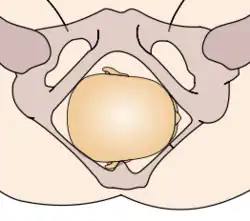

The vertex presentations are further classified according to the position of the occiput, both right, left, or transverse and anterior or posterior:

- Left Occipito-Anterior (LOA), Left Occipito-Posterior (LOP), Left Occipito-Transverse (LOT)

- Right Occipito-Anterior (ROA), Right Occipito-Posterior (ROP), Right Occipito-Transverse (ROT)

The occipito-anterior position is ideal for birth; it means that the baby is lined up so as to fit through the pelvis as easily as possible. The baby is head down, facing the spine, with their back anterior. In this position, the baby's chin is tucked onto their chest, so that the smallest part of their head will be applied to the cervix first. The position is usually "Left Occiput Anterior", or LOA. Occasionally, the baby may be "Right Occiput Anterior", or ROA.[5]